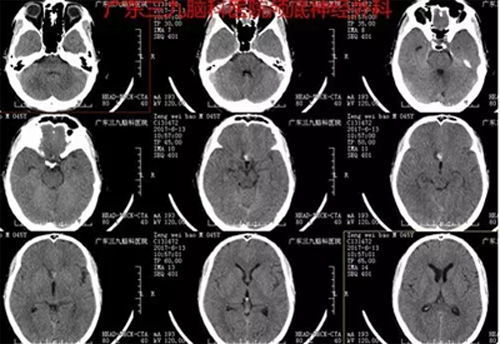

患者曾某,男,45岁。因无明显诱因头痛于6月13日入院,当地医院CTA提示:蛛网膜下腔出血,前交通动脉瘤。入院后完善术前相关检查,6月14日全麻下行“前交通动脉瘤夹闭术”,术程顺利,术后恢复良好。术后诊断:前交通不规则囊状动脉瘤。

图1:术前CT提示鞍区类圆形高密度影